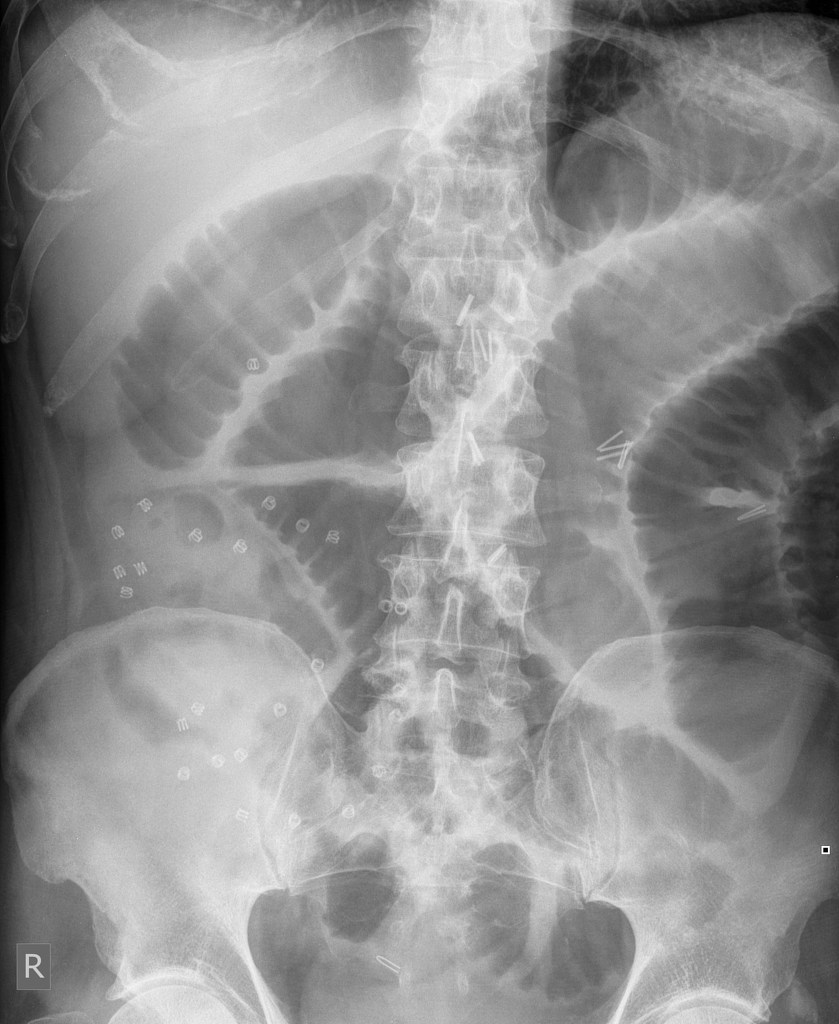

Long standing abdominal bloating and malabsorption

Diagnosis? Sign?

Scleroderma - small bowel involvement

This patient had known long standing scleroderma and demonstrates characteristic small bowel follow-though appearances.

Hide-bound sign

👉 is seen on barium studies of the small bowel in patients with scleroderma.

👉 sign describes a narrow separation between valvulae conniventes of normal thickness despite dilatation of the bowel lumen

Although the term hide-bound is used specifically to describe scleroderma, the same appearance may also be seen in sprue.

The term hide-bound sign was coined by Alfred Horowitz and Morton Meyers in a study published in 1973, although according to their article the appearance had been described prior to that

The term hide-bound was originally used to describe emaciated cattle.